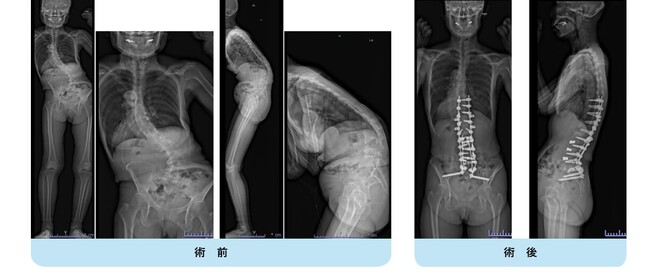

高度腰曲がり・脊柱後弯症・成人脊柱変形の患者さんです。

難治性の腰痛、バランス不良により歩くことも困難な状態でした。

腰椎側方経路椎体間固定術と後方矯正固定術を2回に分けて行い、生理的な胸椎後弯・腰仙椎前弯・骨盤前傾が復元されました。

腰痛・歩行障害は改善し、近所のスーパーへ歩いて買い物にも行けるようになり、台所の仕事も痛みなく出来るようになりました。